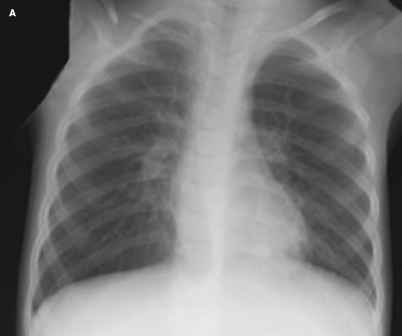

A 4-year-old boy with Down syndrome who underwent chest radiography while hospitalized for fevers, respiratory distress, and hypoxia was found to have an abnormality of the right clavicle. Radiographic results showed hyperinflation of the lungs without a focal infiltrate, indicative of a probable viral pulmonary process, and the incidental finding of a nonunion of the right clavicular bone without callous formation, consistent with congenital pseudarthrosis (A). The parents were not aware of the malformation. The patient had no history of arm or shoulder discomfort or recent or past trauma, especially no birth trauma.

On examination, the clavicular line was symmetric. There was no localized protrusion, tenderness, ecchymosis, erythema, or skin breakdown. The child had full range of motion of his upper extremities. Overall, tone was normal. No other skeletal abnormalities were noted. A chest radiograph taken of the patient in infancy confirmed the presence of pseudarthrosis of the right clavicle.

Affected patients have no pain, limitation of motion, or decrease in strength of the upper extremities and are neurovascularly intact.12 As the patient matures, a painless swelling over the middle third of the clavicle may develop.2 The diagnosis is usually made incidentally when reviewing radiographic imaging for other clinical concerns, as in this patient. Radiographs show separa- tion in the mid-third region of the clavicle; the fragments have round, smooth edges, and no callous formation (B).6,11